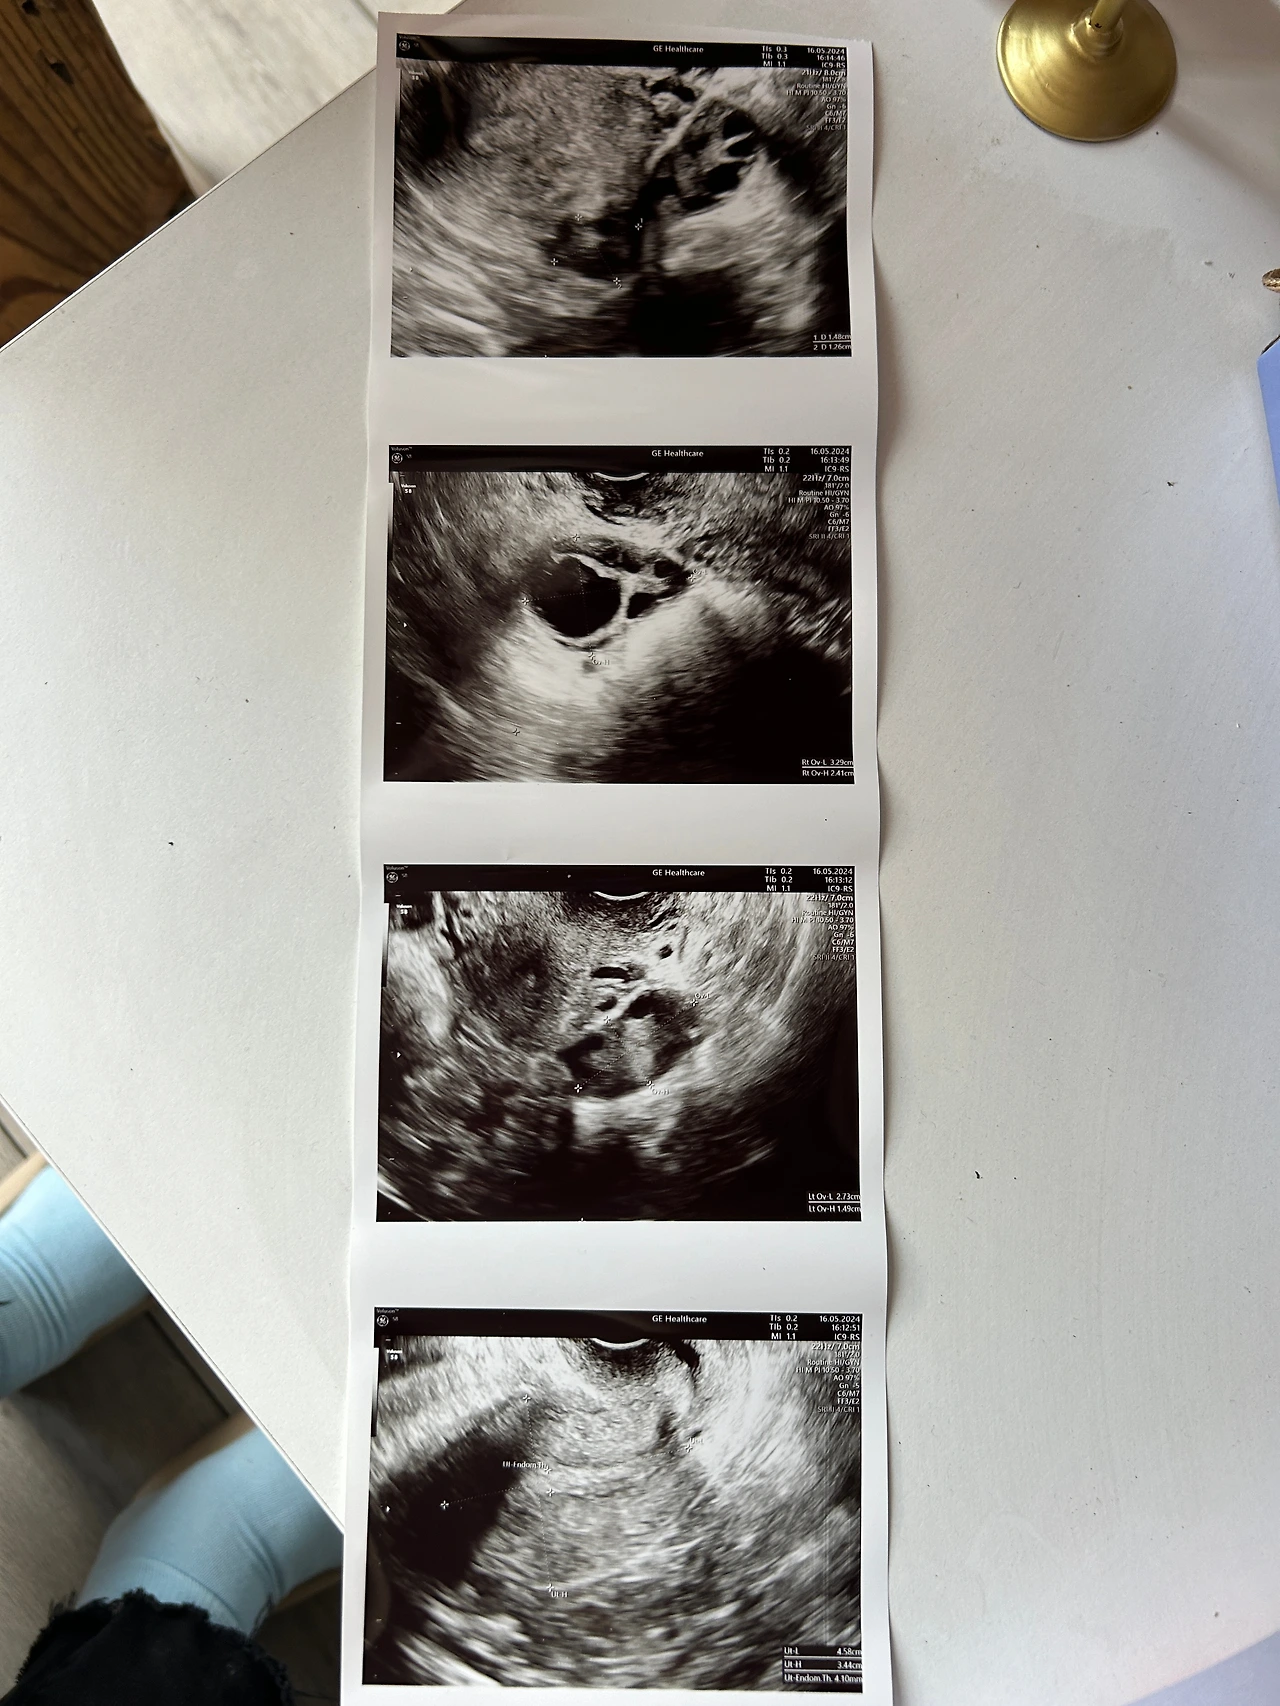

바로 질 초음파 하면서 영상 보면서 여기는 문제없다 여기에 이거 보이냐 하며

영상을 같이 보면서 설명해 줘서 되게 꼼꼼하다고 느꼈다.

아무튼 자궁 내막에 작은 근종이 보이고 더 커질 수 있지만 지금은 크기가 작아서 괜찮다고 했다.

번역된 내용에서는 자궁 후벽의 장막하근종, 자궁 내막에 균질이 있다는 것이다.